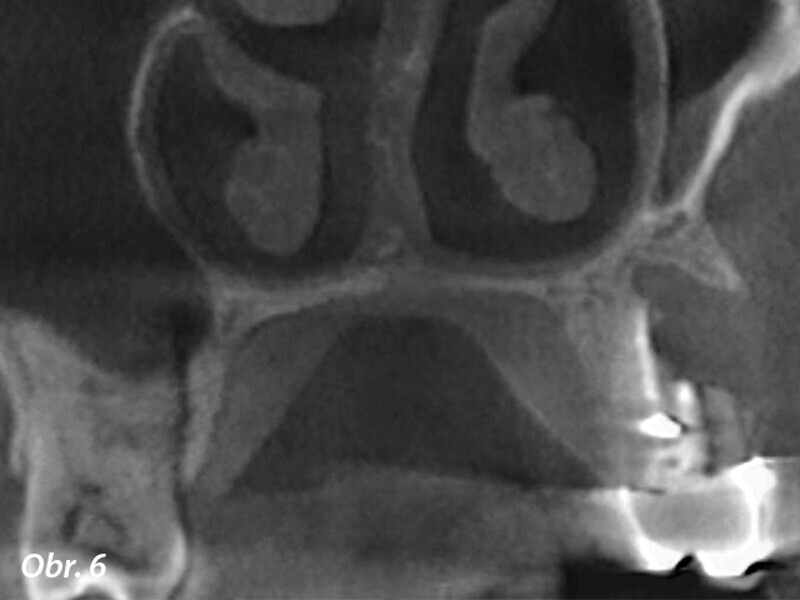

3D technologie v diagnostice a léčbě endodontických onemocnění